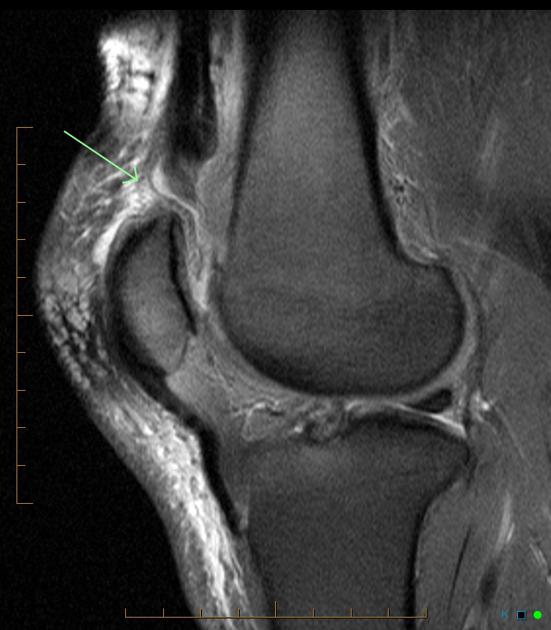

Ved tvivl laves akut MR-skanning,

som altid kan vise læsionen.